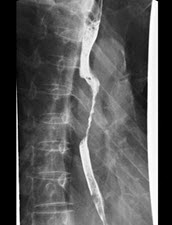

男,16岁,长期的骨骼肌肉畸形,听力障碍,结合图像,最可能的诊断是()

A.马方综合征